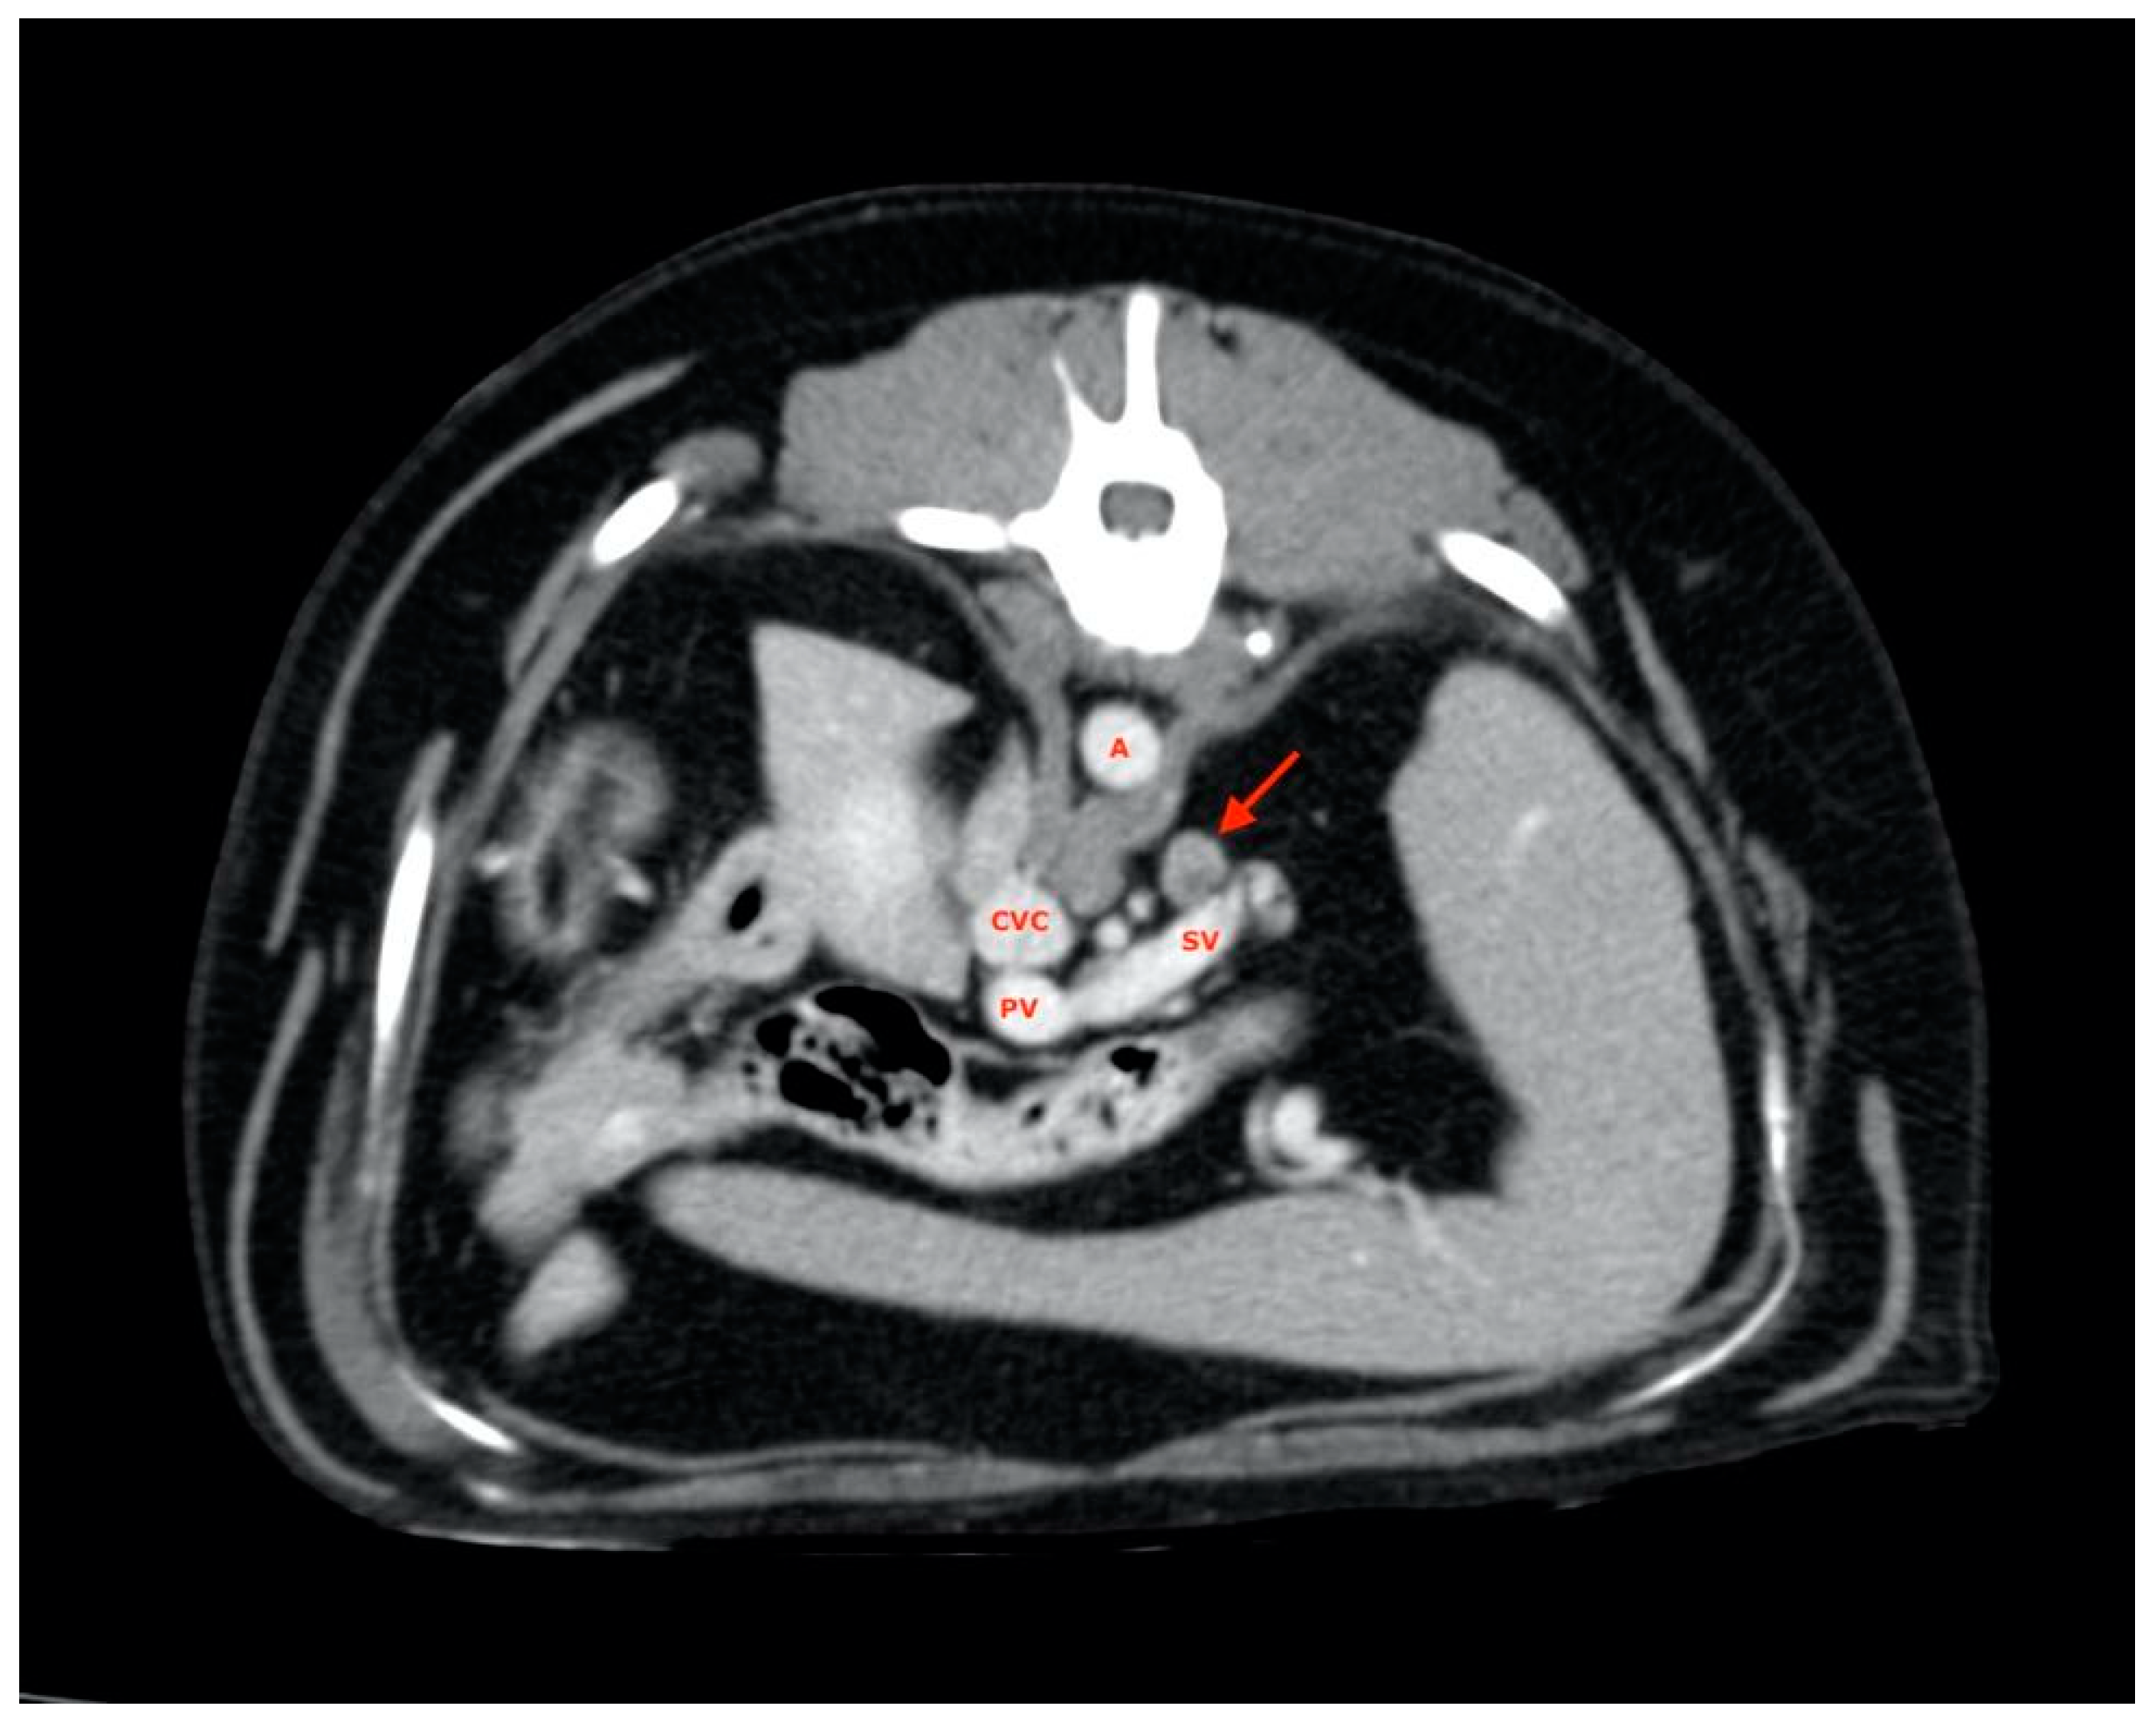

2.4. Procedures

2.5. Measurements